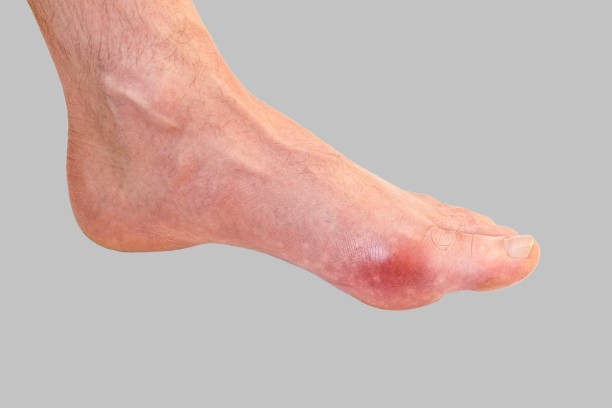

통풍 증상 네 번째는 급성 통풍 발작인데 엄지발가락, 발목 등 한 곳의 관절이 갑자기 빨갛게 부어오르고 손댈 수 없을 정도로 통증이 심한데 발뒤꿈치, 팔목, 손가락, 귀 등에서 나타나며 급성 통풍성 관절염이라고 부르기도 합니다.

통풍 증상 여덟 번째는 발열과 오한을 동반하게 되는데 이 때 나타나는 발열과 오한은 극심한 통증을 유발하는데 이 때는 통풍을 의심할 수 있습니다.